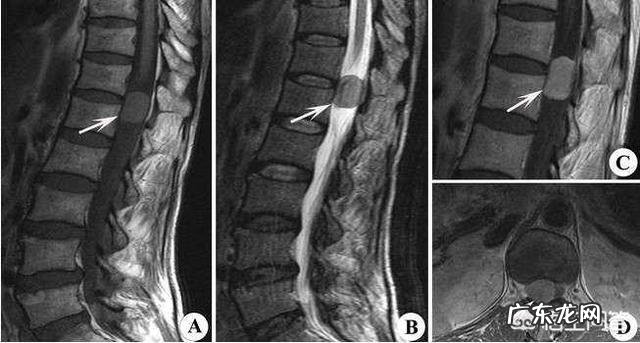

1、椎间盘源性腰痛:椎间盘发生病变 , 纤维环或者软骨终板的破裂 , 血液循环接触髓核组织后产生的自身免疫性炎症而引发了疼痛[1] 。

4、腰骶移行椎与腰痛有关:骶部移行椎是脊柱发生过程中一种十分常见的分节异常 , 主要表现为末节腰椎的一侧或两侧横突增大、并与骶骨形成不完全或完全骨性融合[4] 。

“腰疼”至少有十大病因 , 必须一一查清 , 做好诊断和鉴别诊断 , 避免和防止误诊误治的发生 。

腰痛是一个症状 , 造成疼痛的可以有很多疾病 , 不是腰痛就考虑腰椎间盘突出症 , 还有很多其他的诱因也可造成腰痛 , 像原发性肿瘤、腰椎结核、强制性脊柱炎、腰肌劳损、腰椎小关节紊乱 , 肾结石等都可以诱发腰痛 。